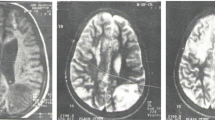

Clinical heterogeneity is commonly observed in Wilson disease (WD), including cases with identical ATP7B mutations. It is thought to be an outcome of impairment in other genes involved in cellular copper homeostasis in addition to the mutations in the ATP7B gene. ATOX1, a copper chaperone that delivers copper to ATP7B, is a potential genetic modifier of WD. In the present study, we analyzed the genetic variations in the ATOX1 gene in 50 WD patients and 60 controls. We identified four novel variants, of which, the coding region variant c.40G > A, p.(Gly14Ser) was observed in 2% alleles. Interestingly, p.(Gly14Ser) was seen with an early onset age, reduced serum ceruloplasmin level and manifestations of liver and brain in a WD patient unlike the other having identical ATP7B mutation but normal ATOX1 alleles. Further, computational analysis predicted that p.(Gly14Ser) substitution, in the critical copper binding motif (MXCXG14C) of the protein, affects the protein–protein interaction involved in copper sharing and transfer between ATOX1 and ATP7B-MBD4. Our findings suggest that p.(Gly14Ser) variant of ATOX1 might play a role as a genetic modifier leading to phenotypic variation in WD.